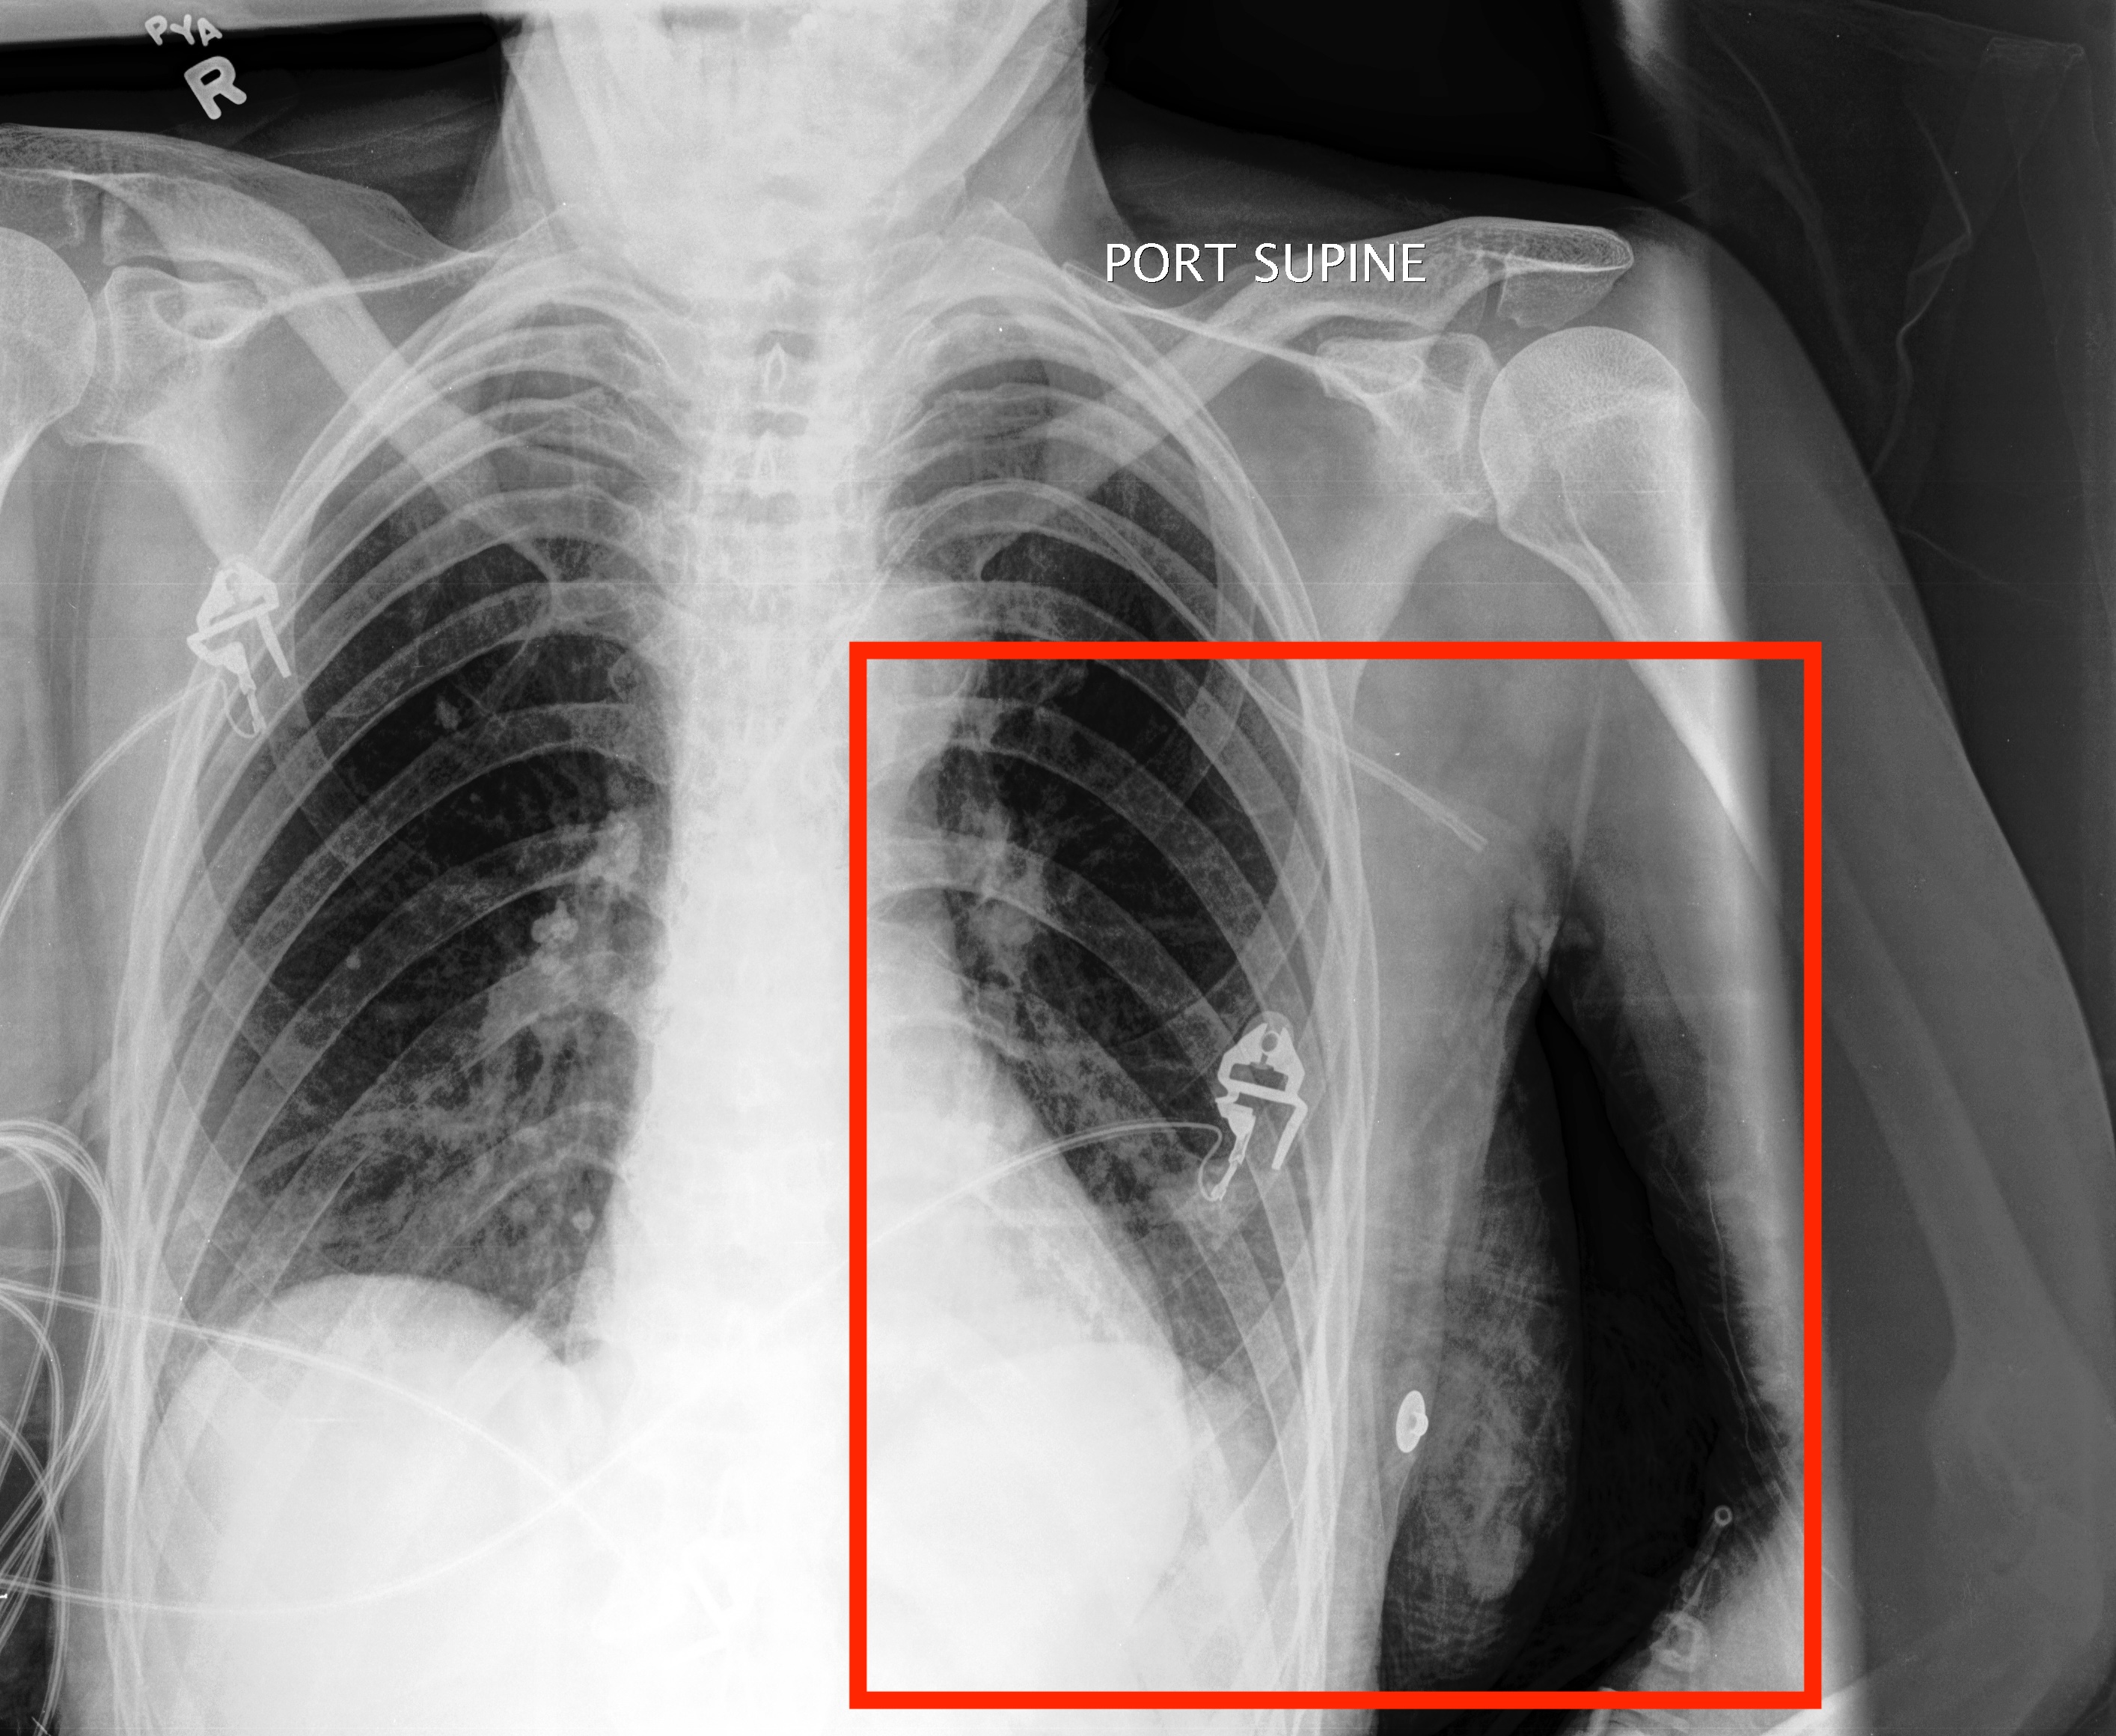

Refer to caption

Figure 4: Model outputs annotated by clinical experts. QoQ-Med correctly reasons from modality-specific clinical knowledge, generates bounding boxes, and outputs the correct predictions in most instances except (c). (e) demonstrates the model’s ability to synthesize multimodal inputs with reasoning. The bounding boxes correctly highlight the salient regions related to the reasoning steps when one is present.

Clinician relevance annotations. App. D.4.2 provides a breakdown of clinician-annotated reasoning traces, revealing that the model mostly generates contents highly relevant to the diagnosis, with minimal output judged as irrelevant. We observe that the model often correctly recalls relevant clinical knowledge, which help guide the model by providing associative context. For example, in Fig  4(a), the model correctly recalls different signs of hemorrhage on CT, such as darker or whiter tissues, and relates this context to specific parts of the image to make a correct prediction. In Fig. 4(c), the model correctly identifies the presence of a pacemaker, indicating a support device, but subsequently concludes that there are no additional abnormalities, ultimately leading it to predict “No finding”. This suggests that while the model’s final predictions may be incorrect, its intermediate reasoning often reflects clinically relevant patterns.

Bounding box quality. Fig. 3(b) demonstrates that the model identifies bounding boxes correlated with the ground truth annotations, with the IoU exceeding the best open source models while reaching a similar performance as the closed-source reasoning model o4-mini. From Fig. 4, we also see that the outputs by the model are sufficiently aligned with the reasoning process, allowing the clinicians to confirm the model’s predictions while cross-referencing the source image.